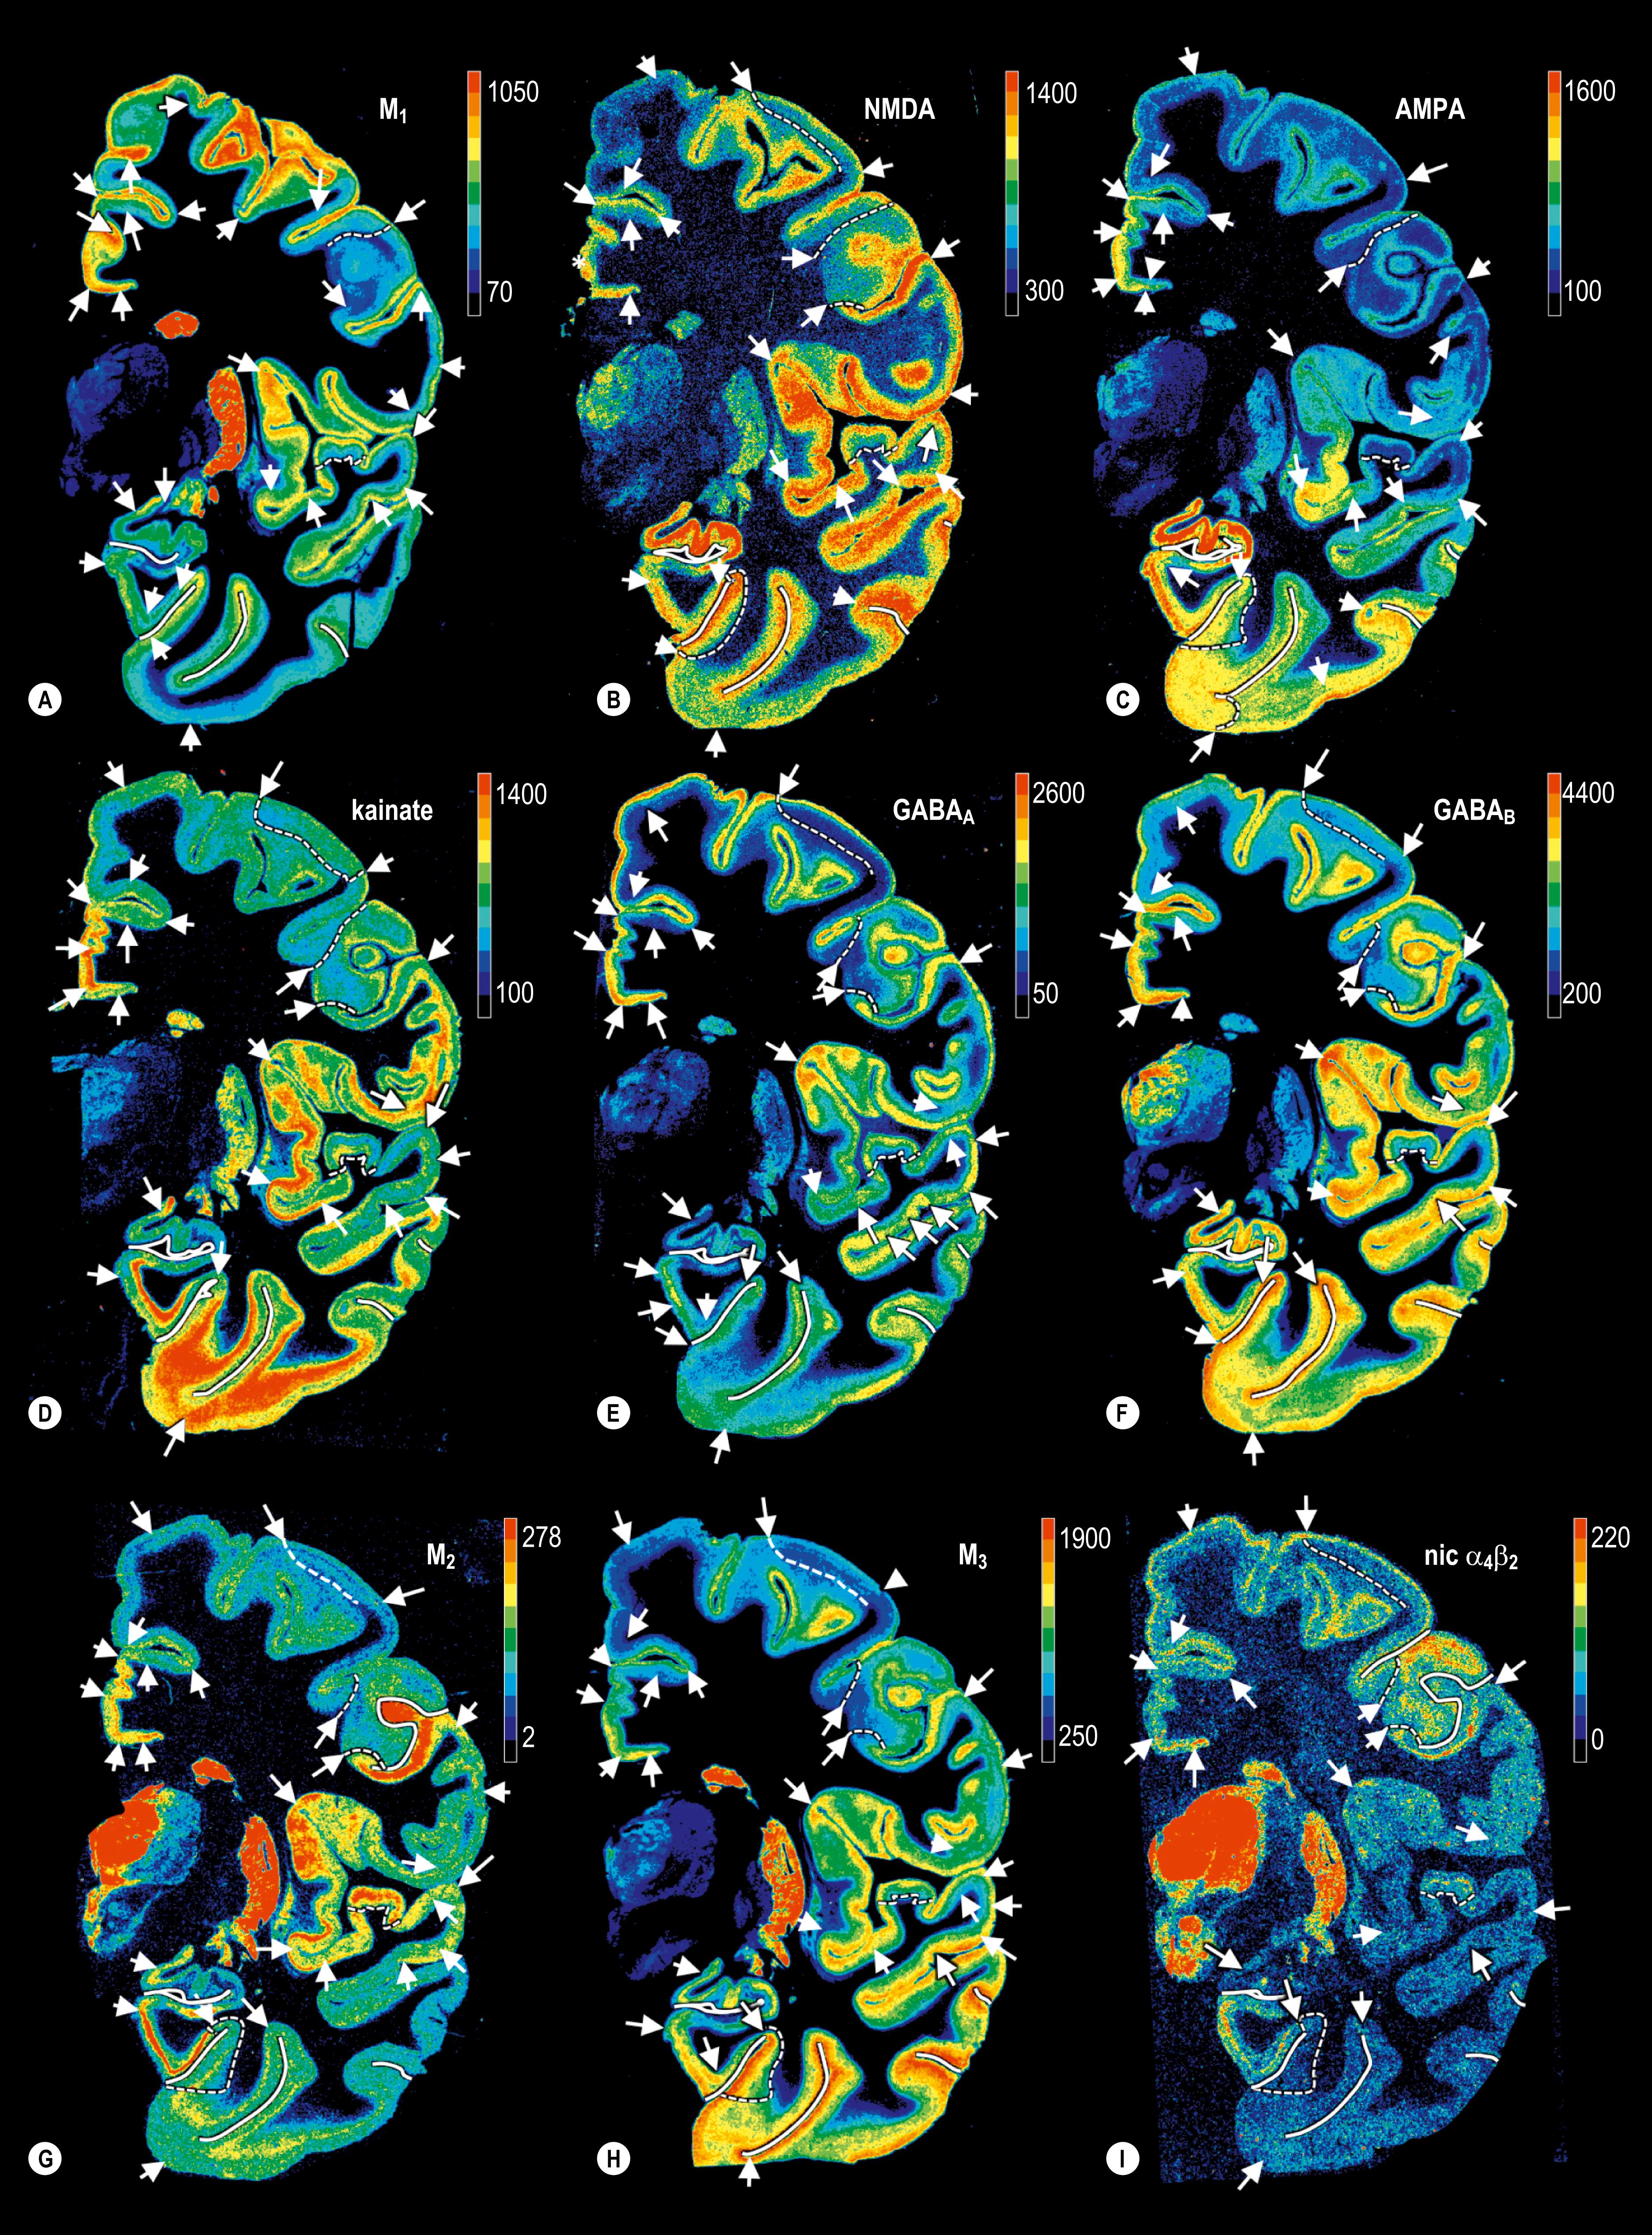

The development of in vitro tissue slice binding techniques and quantitative autoradiography has enabled the visualization and quantification of neurotransmitters and their receptors within individual cortical fields. Although a single receptor type can characterize the borders of functionally and cytoarchitectonically defined cortical regions, in most cases only the characterization of the expression patterns of multiple receptors in the same cortical region can provide the criteria for a multimodal parcellation. These multi-receptor expression patterns are the characteristic fingerprints of each cortical area ( Figs 32.20 32.22 ). They facilitate detailed mapping of the human cerebral cortex and provide insight into the hierarchical relationships of these areas and the principles of their organization into structurally and functionally defined networks ( , , , , ). Maps of cortical neurotransmitters are important for understanding the neuropathological signatures of neurological and psychiatric disorders and the development of new molecules that can selectively modulate the activity of individual areas.

Fig. 32.20, Receptor analysis of the occipital areas. A , Distribution of three receptors in a coronal slice of the occipital cortex. B , Receptor fingerprints of areas V1 and V2.

Fig. 32.21, Multi-receptor fingerprints of cortical areas of the human brain. V1, primary visual cortex; V2v, ventral part of the secondary visual cortex; 1, somatosensory system; 3b, BA1 and BA2 areas of the primary somatosensory cortex; 41 and 42, primary and secondary auditory cortex; 4, primary motor cortex; 44 and 45, areas of Broca’s region; PFm, inferior parietal area; 10L, frontopolar area; 9, BA9; 24, BA24; 38, BA38.

Fig. 32.22, Hierarchical Cluster Analysis of receptor fingerprints in the left ( A ) and right ( B ) hemispheres.

Transmitters in the Human Cerebral Cortex

A single receptor type can characterize the borders of functionally and cytoarchitectonically defined cortical regions. Prominent examples are the M 2 receptor and the delineation of BA17, area 3 and BA41 from surrounding cortical areas, or the identification of mossy fibre terminations on kainate receptors in the hippocampus. However, in many cases only the comparative evaluation of the expression patterns of multiple receptors in the same cortical region provides the criteria for a multimodal parcellation, which cannot be achieved by a single receptor type analysis. These multireceptor expression patterns, the characteristic fingerprints of each cortical area (see Figs 32.20 32.22 ), allow a detailed mapping of the human cerebral cortex and the identification of cortical networks. The analysis of receptor fingerprints reveals cortical regions that belong to the same functional network. For example, analysis of receptor fingerprints in the cingulate cortex has revealed four regions that are differentially involved in emotional processing, mediation of motor and cognitive processes via premotor planning with motivational characteristics, spatial orientation, memory and visuospatial functions ( ).

The fingerprints of BA44 and BA45 are more similar to each other than they are to those of the ventral premotor cortex or the ventrally adjacent BA47, often interpreted as part of Broca’s region. Subsequent analysis of many functionally identified language and non-language regions revealed that the receptor fingerprints of BA44 and BA45 belong to a complex system of language-related areas in the left hemisphere that consists of the subdivisions of BA44 and BA45, BA47, the secondary auditory area BA42, and a region in the posterior part of the superior temporal gyrus and sulcus within Wernick’s area ( , ; see Fig. 32.22 ). The fingerprints of the areas in this functional system clearly differ from those of primary sensory cortical areas, multimodal areas of the inferior and superior parietal lobules, higher extrastriate visual areas, BA32 and the primary motor cortex. A separate analysis of the fingerprints of the right and left hemispheres revealed a notable interhemispheric difference that underlines the lateralized language function.

Fingerprint analysis of the different areas of the inferior parietal lobule demonstrated a very close relation between BA39 and the extrastriate area V3v ( ), supporting the notion that at least the posterior part of BA39 is a hub in the ventrodorsal visual stream ( ). Hierarchical cluster analysis of the receptor fingerprints of fusiform areas FG1 and FG2 argues for their position between the ventral visual stream and multimodal association areas of the inferior parietal lobule ( ). FG1 and FG2 differ from the early visual areas of the ventral stream: a principal component analysis found that all visual areas were separated from nearly all other cortical areas studied, but FG1 and FG2 were segregated from early visual areas, indicating their close association with multimodal association areas of the inferior parietal lobule ( ).